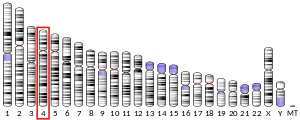

| |||||||||||||||||||||||||||||||||||||||||||||||||||

| |||||||||||||||||||||||||||||||||||||||||||||||||||

| |||||||||||||||||||||||||||||||||||||||||||||||||||

| |||||||||||||||||||||||||||||||||||||||||||||||||||

| |||||||||||||||||||||||||||||||||||||||||||||||||||

| |||||||||||||||||||||||||||||||||||||||||||||||||||

| |||||||||||||||||||||||||||||||||||||||||||||||||||